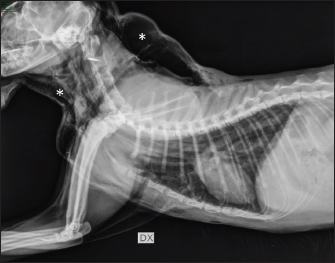

On arrival, venous blood gas analysis revealed mild respiratory acidosis and mild hyperlactatemia (Table 1). The complete blood count revealed moderate thrombocytopenia and neutrophilic leukocytosis (Table 2). Biochemical analysis showed elevated liver and muscular enzyme levels and increased serum amyloid A levels (Table 2). Hypofibrinogenemia (1.36 g/l) with unremarkable coagulation time was evident. All abnormalities were consistent with the traumatic event suspected. Thoracic radiographs confirmed the presence of severe subcutaneous emphysema, associated with moderate pneumomediastinum and mild pneumothorax (Fig. 1). Computed tomography (CT) was scheduled for the following day due to the high suspicion of tracheal injury associated with cervical compressive myelopathy. The cat was hospitalized at the intensive care unit under strict monitoring, minimizing manipulation as much as possible. Fluid therapy was set at 2 ml/kg/h IV of lactated Ringer’s solution, together with analgesic therapy with methadone at 0.1 mg/kg IV every 4 hours, and antibiotic therapy with ampicillin-sulbactam 20 mg/kg IV every 8 hours. The cat was mildly symptomatic for the pneumothorax and was therefore managed conservatively. The following day, the clinical parameters were stable, and a progressive reduction of the subcutaneous emphysema and pneumothorax was noted; therefore, the patient was sedated with 0.2 mg/kg of methadone intravenously (IV) and 2 µg/kg of dexmedetomidine IV, and then placed in a VetMouseTrapTM to avoid intubation and general anesthesia. CT scans confirmed the moderate to severe subcutaneous emphysema, pneumomediastinum, and mild pneumothorax (Fig. 2). A dorsal parietal deformation of the cervical trachea of approximately 1 cm in length was observed, causing a mild reduction in the dorsoventral tracheal diameter. There were no other airway injuries. An incomplete fracture line of the caudal margin of the C4 vertebral arch was observed. The fracture line appeared slightly left-lateralized, with a caudal bone fragment approximately 2 mm long and 5 mm wide. This fragment was dislocated into the vertebral canal, narrowing the dorsoventral diameter, with subsequent compression of the spinal cord (Fig. 3). The CT scan confirmed the suspicion of C4 vertebral fracture and tracheal rupture. Endoscopic evaluation of the upper airways and surgical treatment with a dorsal approach for spinal decompression were scheduled for the following day.

Fig. 1. Thoracic radiography (lateral view) performed upon patient arrival. Note the severe subcutaneous emphysema (white asterisk) in the head and neck region combined with moderate pneumomediastinum and mild pneumothorax.